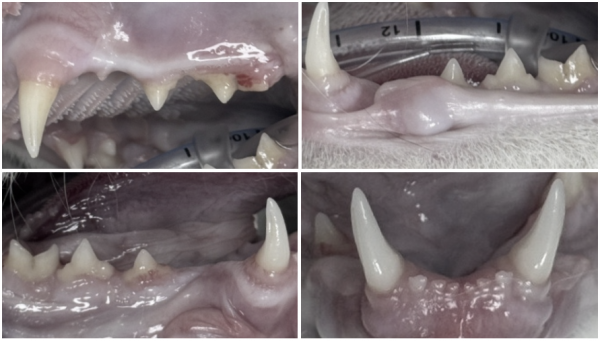

삼동이(가명)는 건강검진과 치과 검진을 위해 내원한 고양이입니다.

기본 검사에서는 감기 증상 외에는 특별한 이상이 없었고,

마취 후 구강 검사를 진행했습니다.

검진 과정에서 우측 송곳니가 반대쪽보다 짧아져 있는 모습이 확인되었습니다.

아래쪽에서 빨간 구멍처럼 보이는 노출된 치수관이 발견되었습니다.

이 치아 상태는 치아 파절로 인해 신경이 노출된 상태이며,

이 구멍을 통해 세균이 치아 내부로 침투하고 있다는 의미입니다.

이는 고양이 송곳니 부러짐에서 흔히 발생하는 합병증 중 하나입니다.